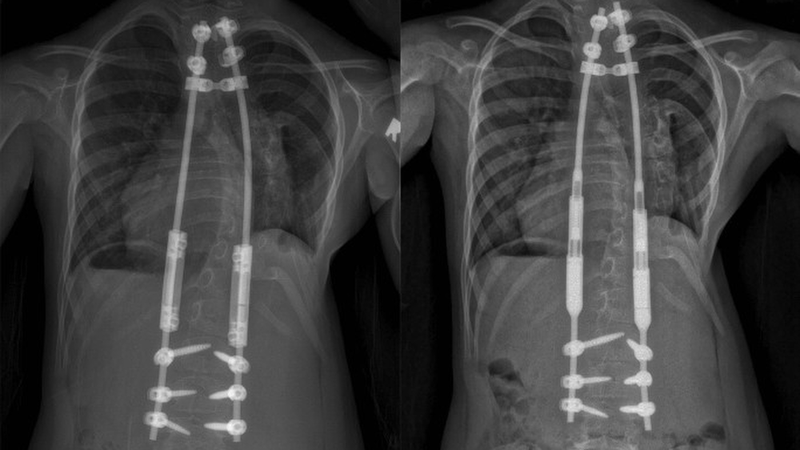

Khi chứng vẹo cột sống bẩm sinh đủ nghiêm trọng để cần điều trị, trẻ thường cần phải phẫu thuật. Nẹp và các phương pháp điều trị không phẫu thuật khác thường không hiệu quả đối với chứng vẹo cột sống bẩm sinh. Điều trị phẫu thuật sẽ phụ thuộc vào độ tuổi và giai đoạn tăng trưởng của bé.

Các phương pháp phẫu thuật cho trẻ mới biết đi và trẻ bị cong vẹo cột sống bẩm sinh:

Phương pháp phẫu thuật cho thanh thiếu niên và thanh thiếu niên bị vẹo cột sống bẩm sinh:

Phẫu thuật hợp nhất đốt sống là phương pháp điều trị phẫu thuật phổ biến nhất cho chứng vẹo cột sống nặng ở thanh thiếu niên. Phẫu thuật làm thẳng cột sống và củng cố xương để nó sẽ không còn cong bất thường nữa. Trong 6 đến 12 tháng sau khi phẫu thuật hợp nhất đốt sống, cột sống sẽ liền lại theo cách tương tự như cách xương gãy lành lại. Con bạn có thể cần phải đeo nẹp trong thời gian này.